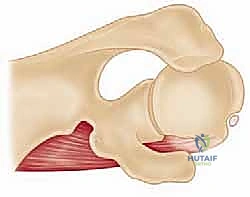

In cases of post-traumatic arthritis, catastrophic cartilage damage associated with a single high-energy event (such as a severe fracture-dislocation) or repetitive microtrauma overwhelms the intrinsic, albeit limited, repair mechanisms of the shoulder joint. The natural history of glenohumeral arthritis, regardless of the precipitating etiology, is characterized by progressive stiffness, intractable pain that frequently awakens the patient at night, and profound functional impairment in activities of daily living. Patients with primary osteoarthritis and post-traumatic variants typically develop a progressive, highly characteristic loss of external rotation. This restriction is primarily driven by the severe contracture of the anterior capsule and the coracohumeral ligament. This asymmetric capsular contracture obligates posterior translation of the humeral head during active motion, leading to eccentric posterior glenoid wear, posterior subluxation, and the formation of large, characteristic osteophytes, particularly along the inferior humeral neck (the so-called "goat's beard" osteophyte). Notably, full-thickness rotator cuff tears are distinctly uncommon in primary osteoarthritis, occurring in only 5% to 10% of patients, which fundamentally dictates the surgical algorithm toward anatomic rather than reverse reconstruction.

The ligamentous and musculotendinous structures surrounding the glenohumeral joint dictate its dynamic stability, obligate kinematics, and safe surgical exposure. The pertinent musculotendinous anatomy includes the deltoid, pectoralis major, the conjoined tendon (coracobrachialis and short head of the biceps), the rotator cuff, and the long head of the biceps. In the arthritic shoulder with an intact cuff, the anterior and inferior capsular ligaments—particularly the middle glenohumeral ligament (MGHL) and the anterior band of the inferior glenohumeral ligament (AB-IGHL)—become profoundly contracted and fibrotic. This anterior tethering not only restricts external rotation but acts as a pathologic fulcrum, driving the humeral head posteriorly during active elevation and directly exacerbating the asymmetric posterior glenoid wear commonly seen in Walch B-type glenoids.